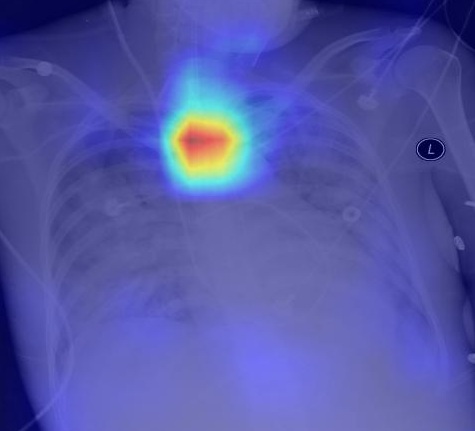

Recognizing normal/abnormal positioning of lines and tubes and their tips with answers derived from the AI attention heat map of a deep learning model

We have developed deep learning AI models trained on chest X-ray images focused on2 stages: (i) segmentation and (ii) classification of lines and tubes. A segmentation model generates masks for any lines and tubes present on a CXR image, which will then be fed to the classification model for identification of the type of line and the position of the tip.

Performance results for central venous catheter (CVC) and endotracheal tube (ETT) tip localisation:

A5 - fold cross-validation of the model was conducted using 5,867 images. The results showed that the classification model can accurately identify the position of the  tip as normal or abnormal, with an area-under-curve (AUC) of 0.902 for central venous catheters and 0.959 for endotracheal tubes.